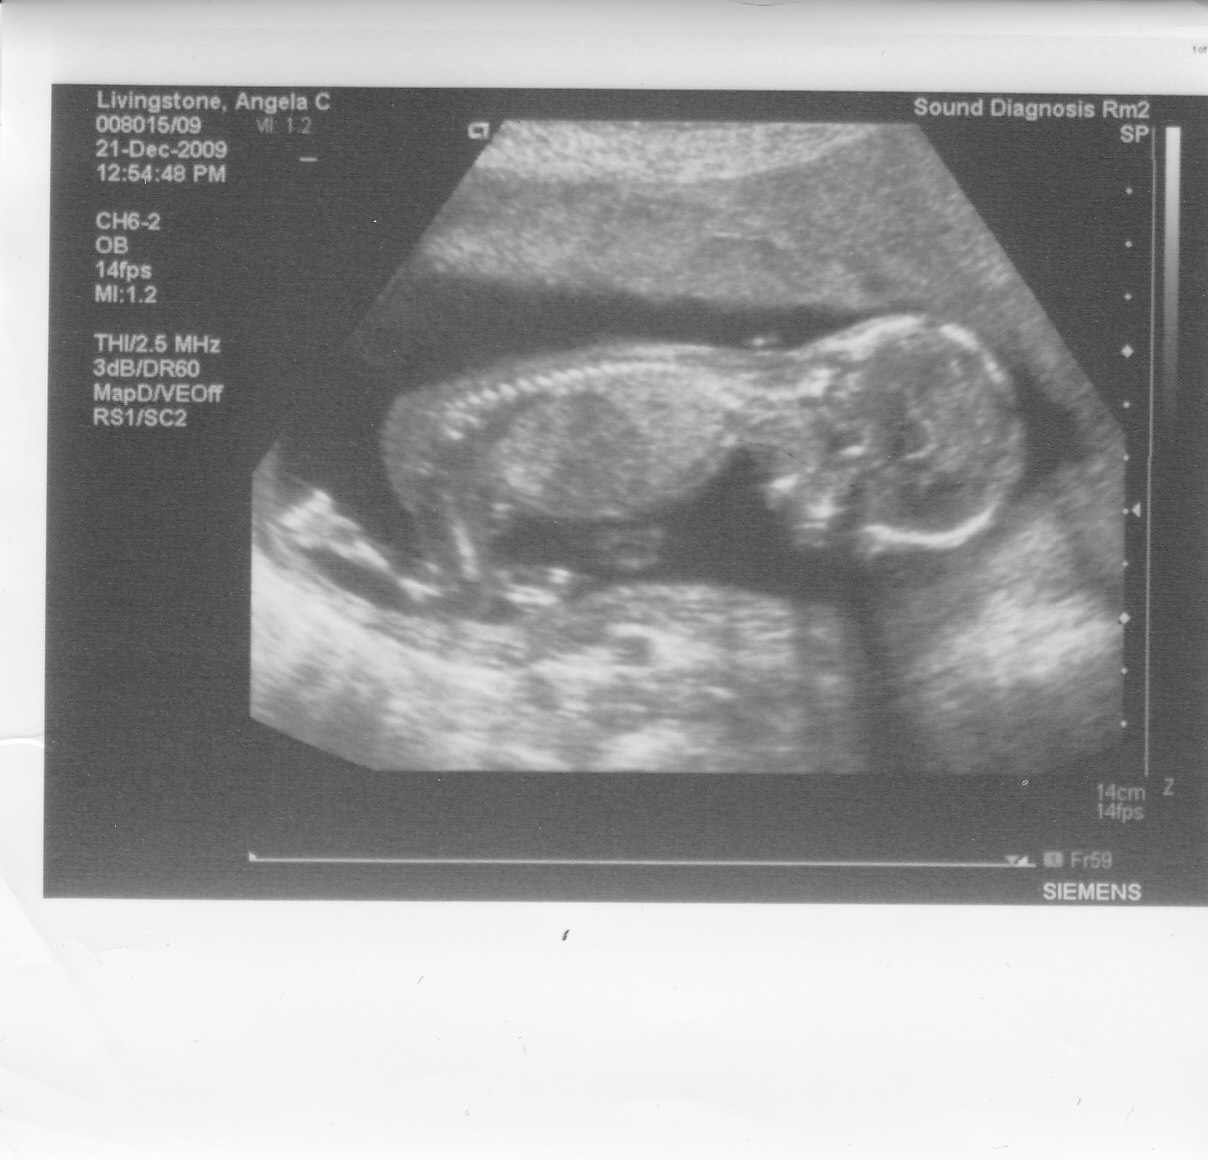

I’m having a son. We just found out that Baby E is Baby Ewan. Woot!!